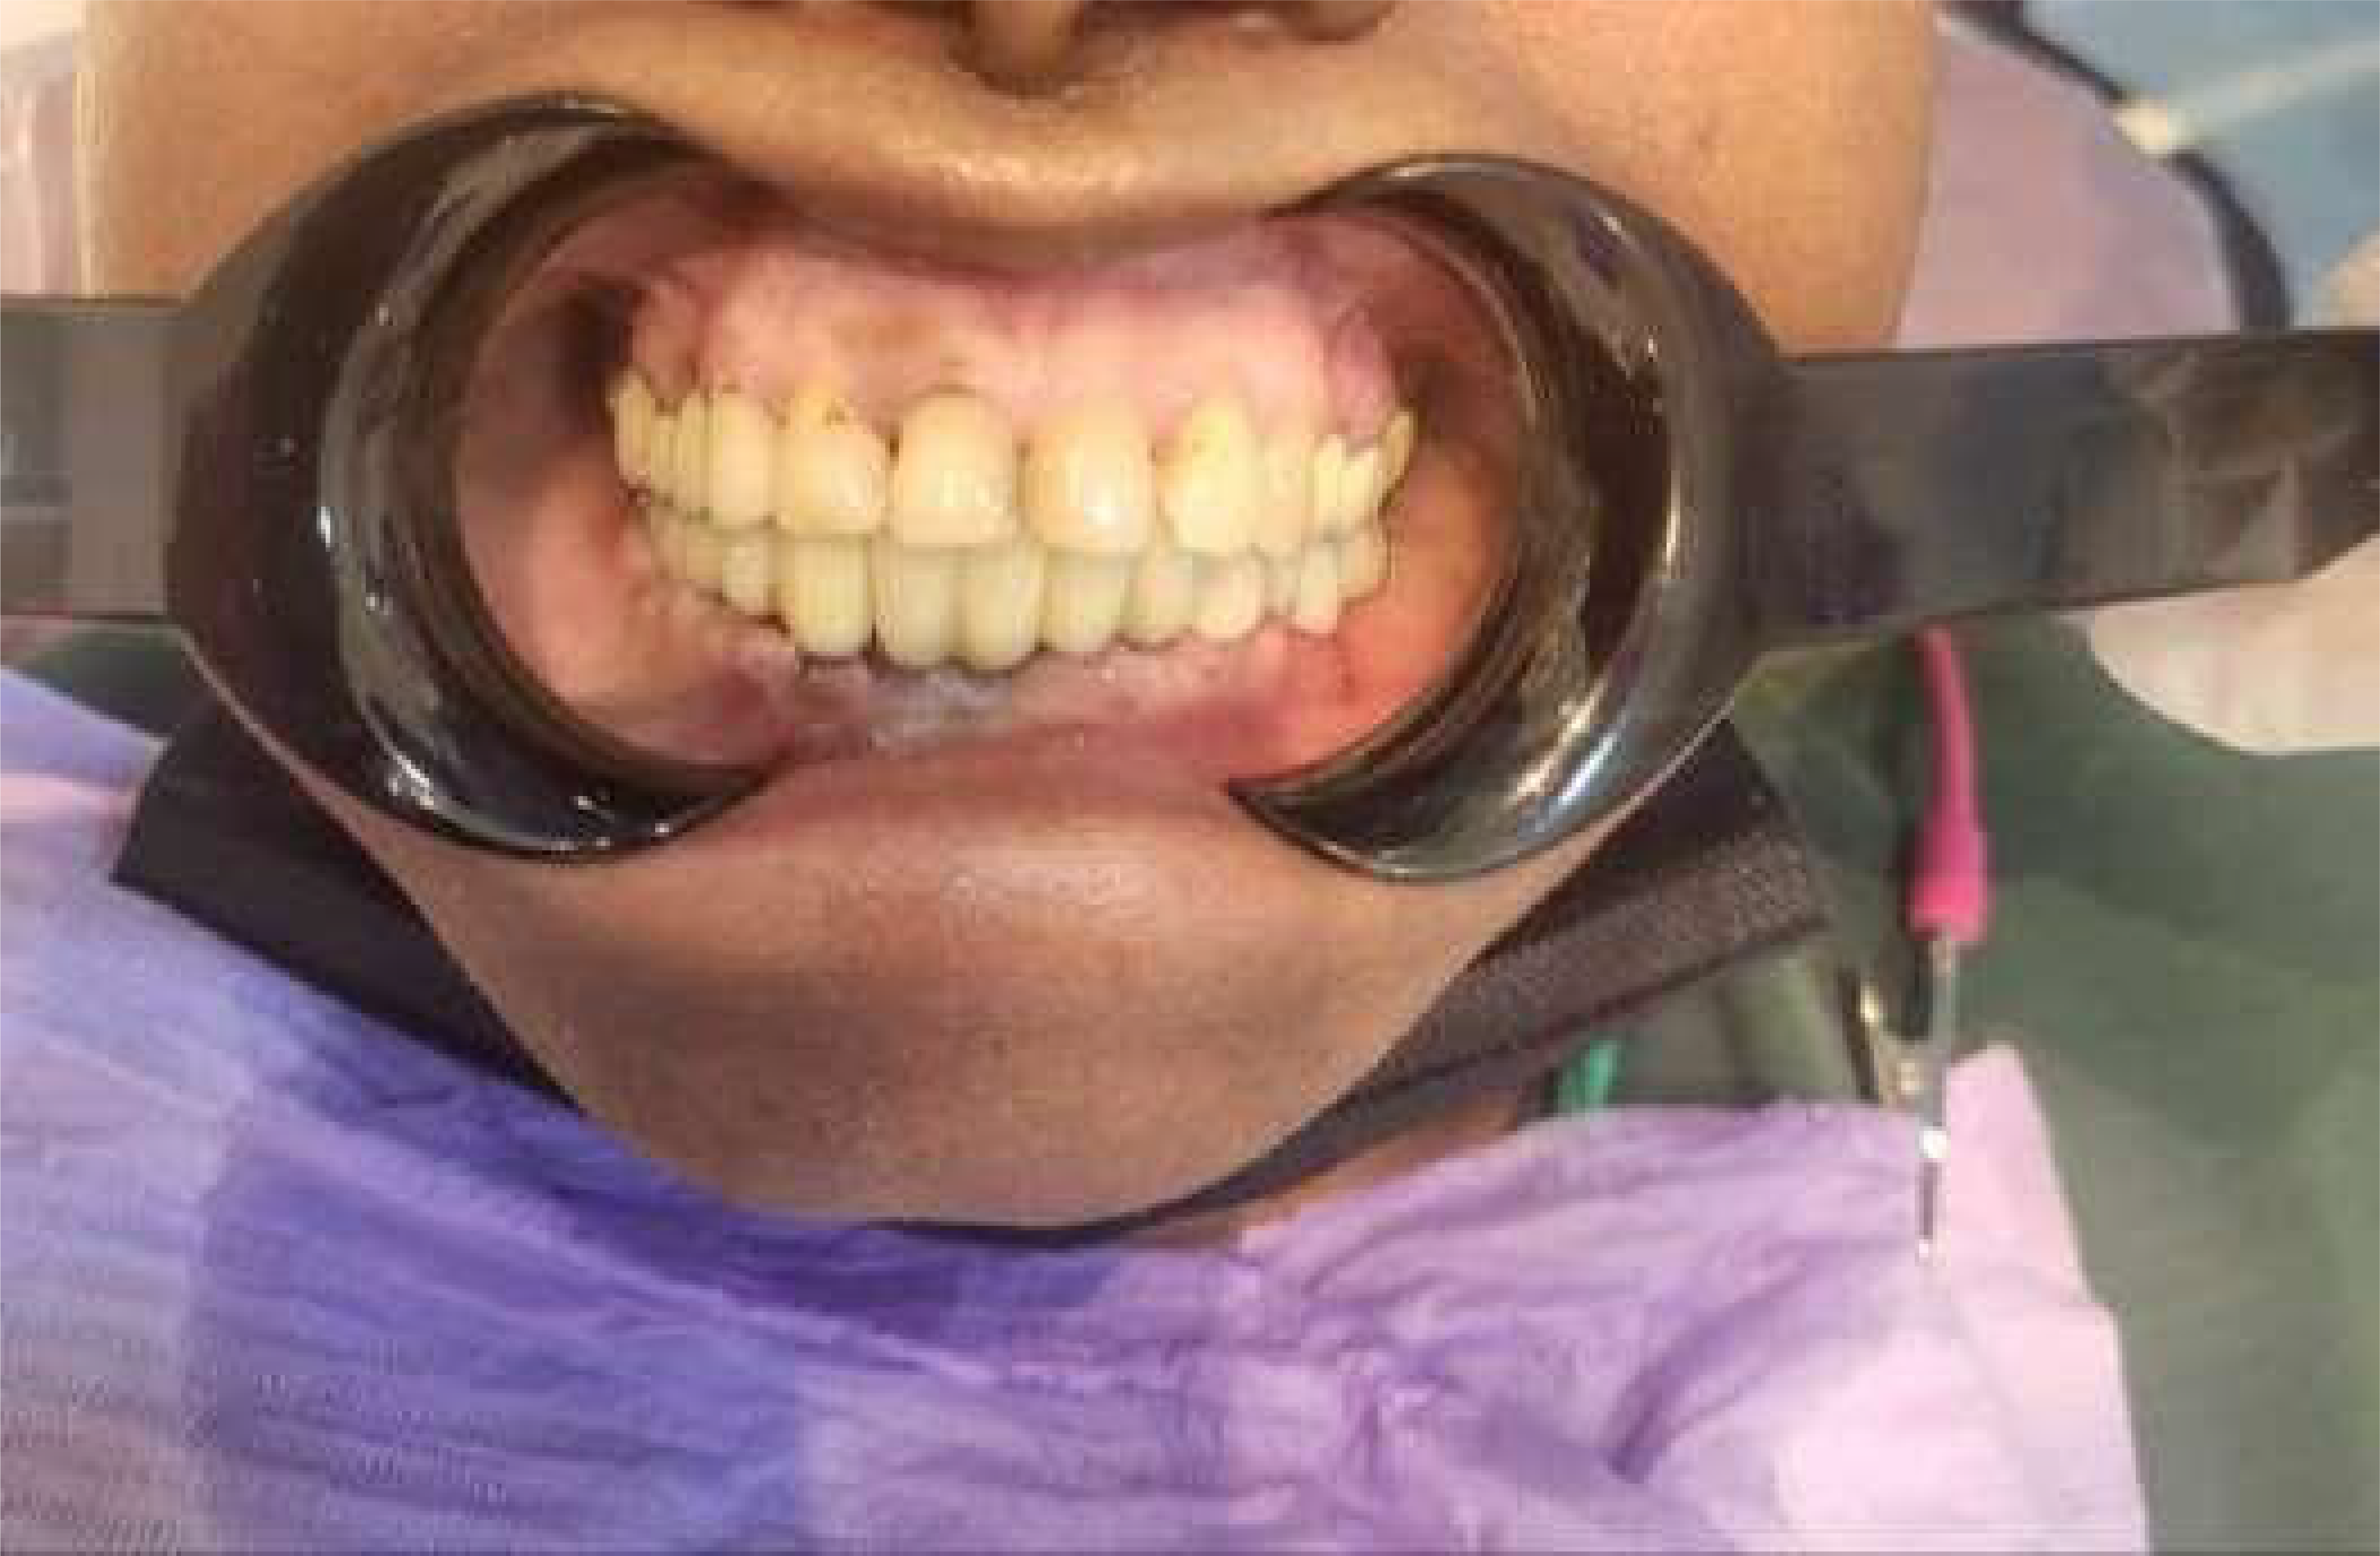

Post-operative clinical picture: Post-op, 6 months: Excellent bone height. Adequate Soft tissue healing